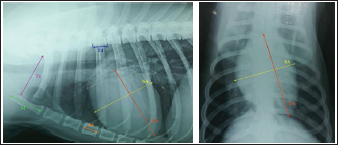

Objective methods for the assessment of cardiac size and shape used in this study were: modified VHS, MHS, SHS, this, and CSI. In each objective methods of cardiac silhouette measurement, the LA and SA were measured in the same way. In LL radiographs, cardiac LA length (mm) was the line extending from the ventral border of the left mainstem bronchus to the most distant ventral contour of the cardiac apex. SA length (mm) was the line drawn perpendicular to the cardiac LA on the widest part of the cardiac silhouette. In DV radiographs, the LA was drawn as the line starting from the dorsal margin of the right atrium projection to the left apex. The SA was drawn perpendicular to the LA at the widest part of the cardiac silhouette (Fig. 1A and B).

Fig. 1. A and B. Measurements of LA and SA in LL (A) and DV (B) views, with marked T4, S4, M, TI length: LA – long axis, SA – short axis, T4 - the length (mm) of the body and caudal disc of the T4vertebra, S4 - the length (mm) of the S4, M – the length (mm) of the M, TI - the length (mm) of a dog’s TI. Modified vertebral heart sizeThe cardiac LA and SA in LL view were measured as previously described, added up, and then transformed from mm into whole and 0.01 of VHS units (v), by dividing the sum of both axes by the length (mm) of the body and caudal disc of the T4 (VHS-LL) (Spasojević Kosić et al., 2007). The same was done to calculate the cardiac VHS in DV radiographs (VHS-DV). Manubrium heart scoreThe sum of the measured cardiac LA and SA (in mm) was normalized by the corresponding M length (mm) according to the method described by Mostafa and Berry (2017). The same was done for both MHS in LL and in DV radiographs (MHS-LL and MHS-DV). Sternebral heart sizeTo determine SHS, the length of the S4 is used as a unit of measurement. The sum of the measured LA and SA in mm was divided by the length of the S4, both for LL and DV radiographs, in order to get SHS in LL and DV (SHS-LL and SHS-DV). Thoracic inlet heart sizeThe sum of LA and SA (mm) was divided by the length of a dog’s TI. The shortest TI was measured from the craniodorsal M to the cranioventral first thoracic vertebra as described by Marbella Fernández et al. (2023a). For this method, cardiac silhouette measurement was performed only in LL radiographs (TIHS-LL). Cardiac sphericity indexCSI was calculated by dividing the cardiac SA by LA obtained from LL and DV radiographs (CSI-LL and CSI-DV) (Guglielmini et al., 2012). Measurement of blood vesselsObjective methods for assessment of blood vessels relevant to the HWD included several measurements (Fig. 2A and B) and calculations. The diameters of blood vessels relevant for the HWD (RCrLA, RCaLA, and VCC) were first measured and expressed in absolute values (mm). The diameters of the vessels were measured perpendicular to their LA. Relative measurements of the relevant blood vessels were expressed as ratios to the T4 (for all three blood vessels), and to the 4.r (for the RCrLA and VCC), to the 9.r (for the RCaLA), and to the Ao (for the VCC). The T4 was measured as described in modified VHS methods. The measurement of the 4.r was done on its proximal part as the smallest diameter. The measurement of the 9.r was measured at its intersection with the RCaLA. The Ao was measured at the descending part (Herrtage and Denis, 1997; Lehmkuhl et al., 1997; Arya et al., 2021).